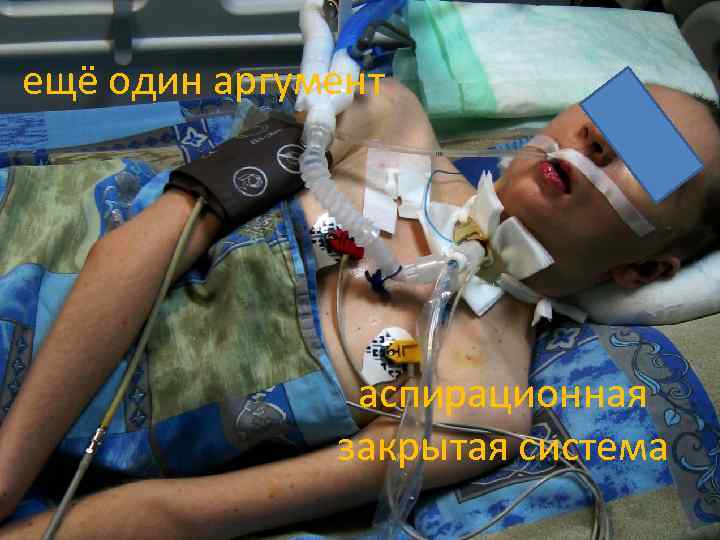

ещё один аргумент аспирационная закрытая система

ещё один аргумент аспирационная закрытая система